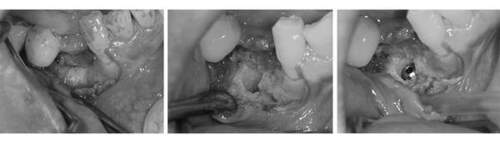

6ヶ月後再び歯茎を切り中の状態を確認。骨がしっかりできており、インプラント手術を行えることが分かると思う。 インプラントを埋めるための穴をあけて、インプラントを埋入した。

麻布十番歯科のインプラント手術の症例

麻布十番歯科のインプラント手術の症例① 麻布十番歯科のインプラント手術の症例② 麻布十番歯科のインプラント手術の症例③

この症例の詳細